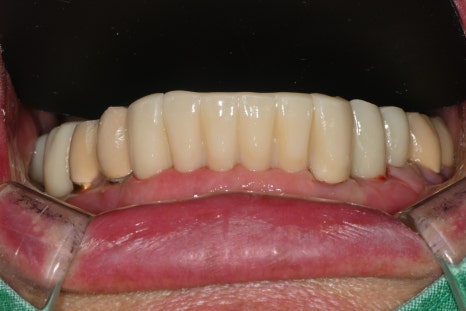

Left photo: The upper prosthesis had good overall fixation and the bite was designed to be stable.

Right photo: The final prosthesis was accurately secured to the implant placed in the extracted site.

Left photo: Front view of the completed prosthesis. Both esthetics and function were restored satisfactorily.